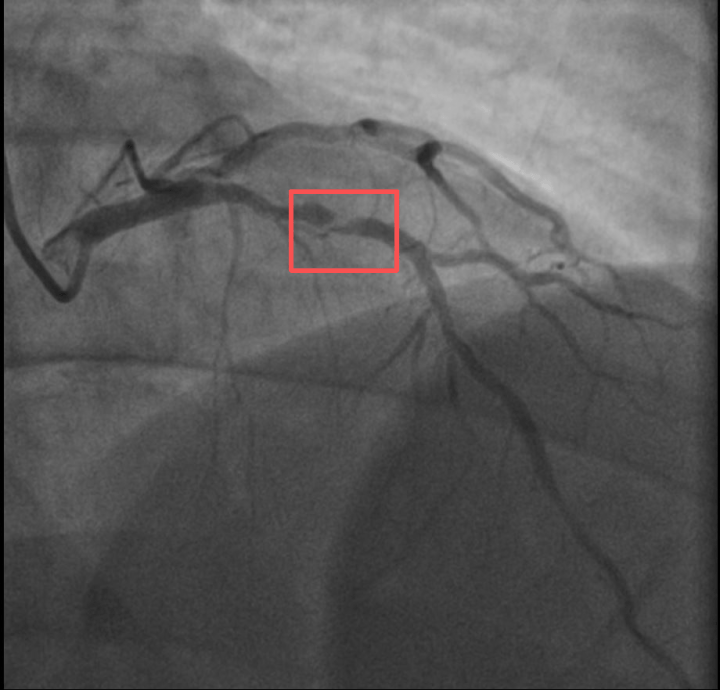

同一天,两个38岁宝爸因急性心梗被送进医院,且都发生在剧烈运动后。都说运动使人健康,这到底是怎么回事?

打了10分钟羽毛球,心脏就受不了了

“我都瘦了10斤了,怎么还是没逃过心梗?”身高173cm,体重约90KG,外形壮实的孙先生是一位羽毛球教练。浙江医院心血管内科吴少泽医师介绍,一年前,孙先生曾因胸闷就诊,被查出心脏右冠中段、远端钙化斑块,以及心脏三支主要血管之一前降支中段60%狭窄。

当时考虑到没有“三高”的危险因素(可能为早发冠心病家族史),孙先生也坚信自己可以通过运动...